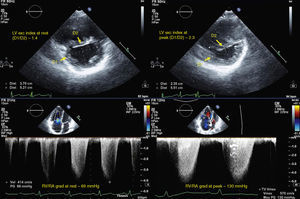

for assessment of RV contractile reserve: in apical 4-chamber view, RV area in diastole (Figure 1) and in systole (to calculate right ventricular fractional area change [RVFAC]), tricuspid annular plane systolic excursion (TAPSE) at the level of the RV free wall, S-wave velocity (with tissue Doppler of the basal segment of the RV free wall), and left ventricular outflow tract (LVOT) velocity-time integral (VTI) (Figure 2). In parasternal long-axis view, LVOT diameter (Figure 1) was assessed only at rest, considering that this dimension does not change with exercise. Stroke volume index (SVI) was calculated on the basis of LVOT diameter, LVOT VTI and BSA.

Figure 2.Echocardiographic parameters of right ventricular contractile reserve in a pulmonary hypertension patient at rest (left) and at peak exercise (right); top – S-wave velocity; middle – TAPSE; bottom – LVOT VTI (used to calculate stroke volume index). LVOT VTI: left ventricular outflow tract velocity-time integral; TAPSE: tricuspid annular plane systolic excursion.